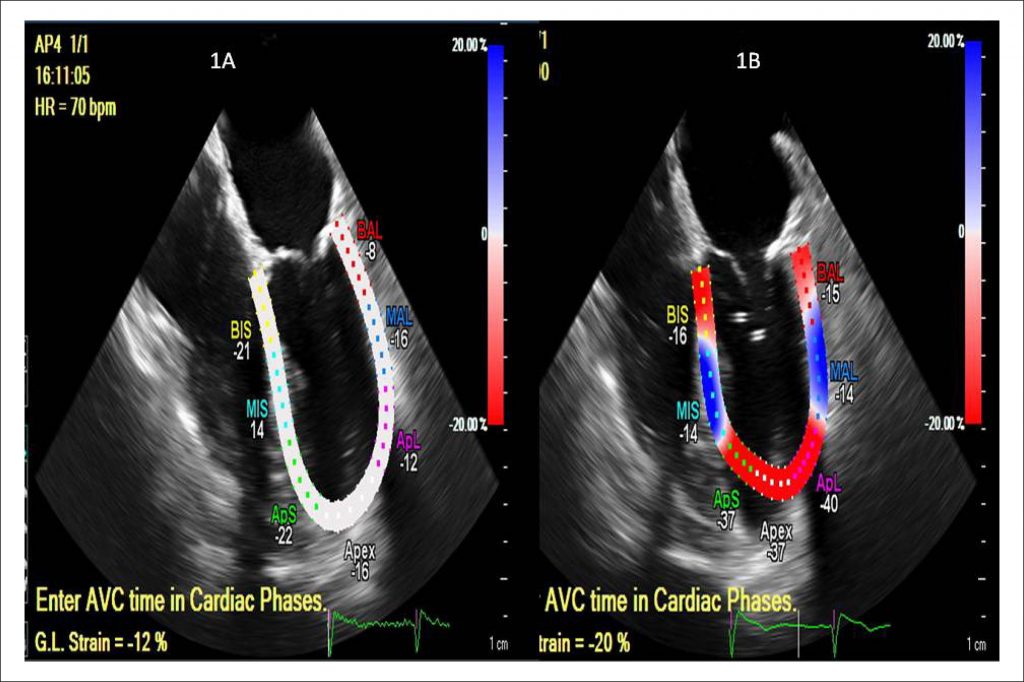

Myocardial Deformation by Echocardiogram after Transcatheter Aortic Valve Implantation

Myocardial deformation (strain) analysis may be done through echocardiography from data obtained by tissue doppler technique or two-dimensional images from speckle tracking, allowing the calculation of longitudinal, circumferential and radial deformations of myocardial fibers., Myocardial strain analysis has recently been used in the evaluation of regional myocardial movement and function and in the systolic time-to-peak calculation which studies cardiac synchronicity and myocardial electromechanical coupling. In clinical practice, conventional echocardiographic investigation is helpful in detecting global myocardial dysfunction and alterations in ventricular segmental contractility. In cardiotoxicity from the use of chemotherapeutics, we may find alterations in cardiac mechanics with no modification of the left ventricle ejection fraction (LVEF). Thus, the analysis of myocardial deformation brings relevant information in the analysis of regional ventricular systolic dysfunction in subclinical conditions.

Similarly, previous investigations have shown that the study of myocardial deformation is able to detect sudden and early alterations in systolic function of valve disease patients, even before they present LVEF modifications.,, This phenomenon is due to a significant decrease in myocardial deformation in three different spatial planes, triggering deformation modifications in the longitudinal, circumferential and radial axes. In patients who present reduced longitudinal myocardial deformation, we can observe radial deformation that is superior to normality parameters, which may result in preserved ventricular function, when estimated by LVEF. Other applications of myocardial deformation include amyloidosis, hypertrophic cardiomyopathy, right ventricular dysfunction, athlete’s heart, cardiac dyssynchrony and valve diseases (mitral insufficiency and aortic stenosis).